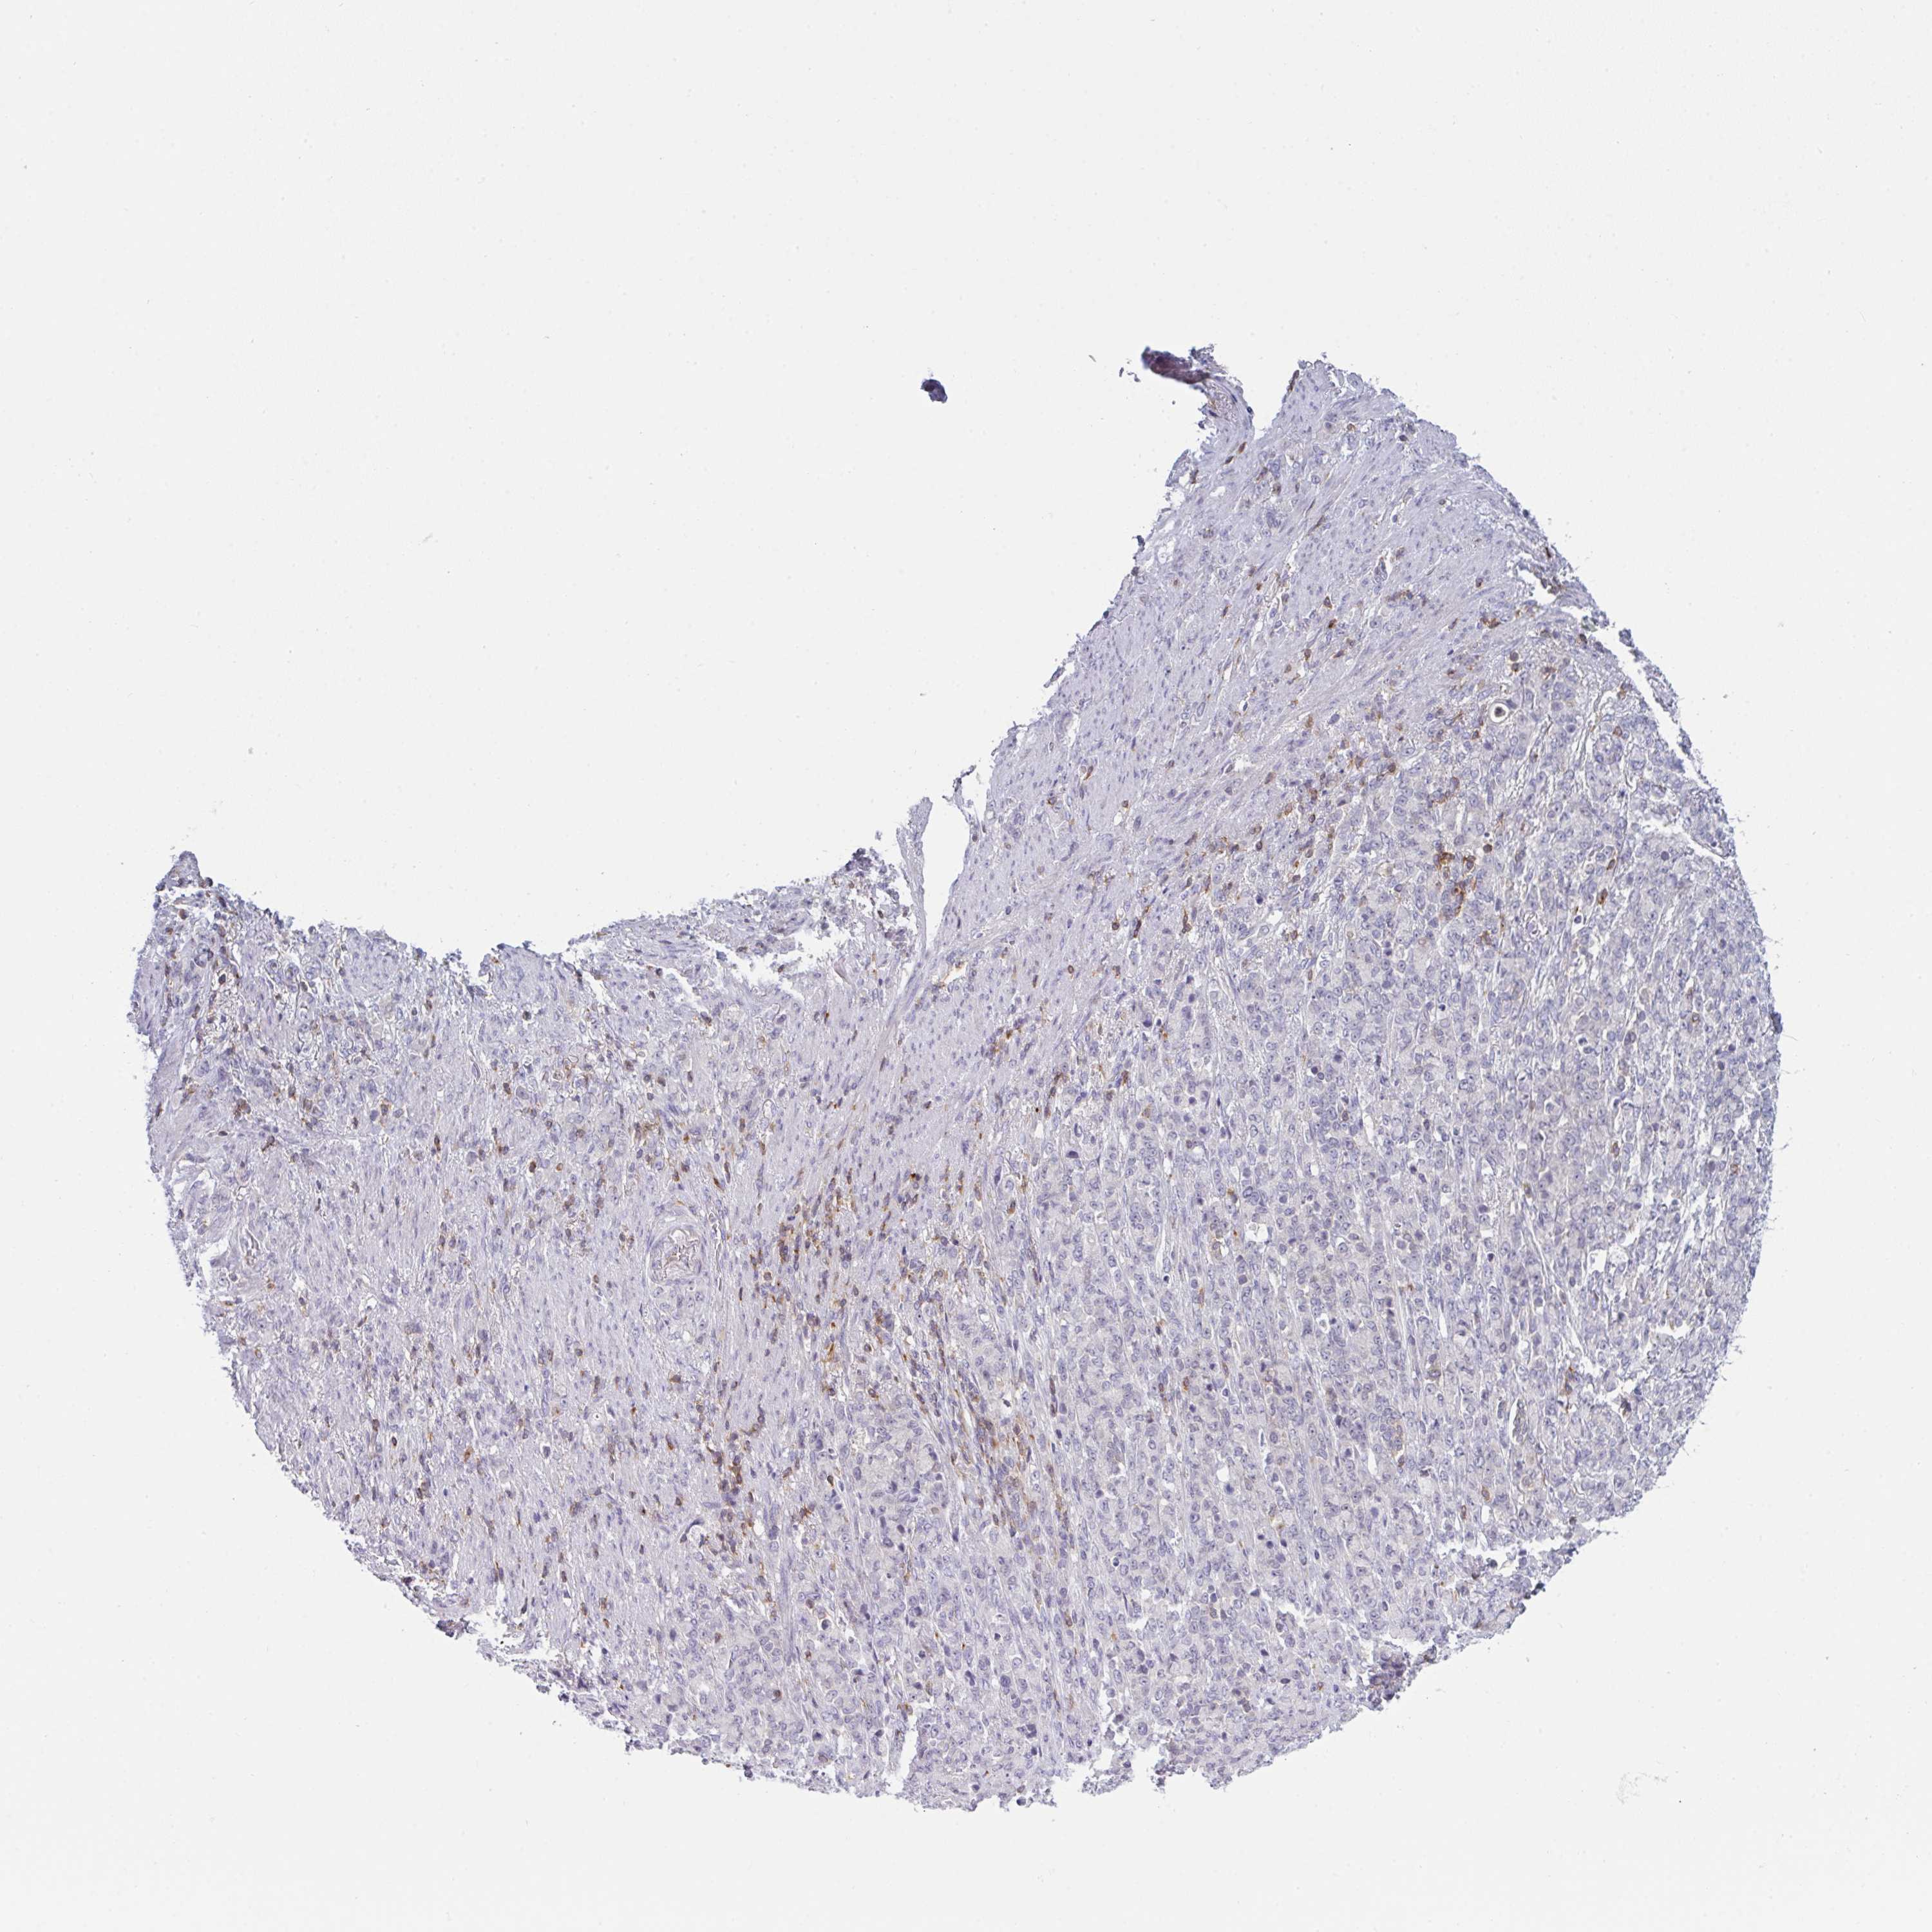

STOMACH CANCER - Protein expressioni

A mouse-over function shows sample information and annotation data. Click on an image to view it in a full screen mode. Samples can be filtered based on level of antibody staining by selecting one or several of the following categories: high, medium, low and not detected. The assay and annotation is described here.

Note that samples used for immunohistochemistry by the Human Protein Atlas do not correspond to samples in the TCGA dataset.

Antibody stainingi

Antibody staining in the annotated cell types in the current human tissue is reported as not detected, low, medium, or high, based on conventional immunohistochemistry profiling in selected tissues. This score is based on the combination of the staining intensity and fraction of stained cells.

Each image is clickable and will lead to virtual microscopy that enables deeper exploration of all samples and also displays staining intensity scores, fraction scores and subcellular localization as well as patient and tissue information for each sample.

Antibody HPA050092

Antibody CAB025368

Staining

High

Medium

Low

Not detected

Intensity

Strong

Moderate

Weak

Negative

Quantity

>75%

75%-25%

<25%

None

Location

Nuclear

Cytoplasmic/membranous

Cytoplasmic/membranous,nuclear

Adenocarcinoma, NOS

Adenocarcinoma, High grade